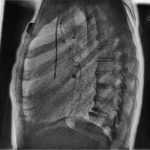

Специалисты ООО “ДРАЙВ” установили в Учреждение здравоохранения “Солигорская центральная районная больница” систему для получения и обработки рентгеновского изображения “Драйв-DR-02”. медицинская […]… далее

Специалисты ООО “ДРАЙВ” установили в Учреждение здравоохранения “Стародорожская центральная районная больница” систему для получения и обработки рентгеновского изображения “Драйв-DR-02”. медицинская […]… далее